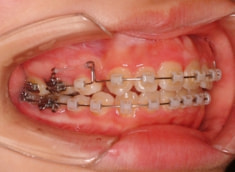

治療法:表の矯正(T21ブラケット)

治療後(1年2ヶ月後)